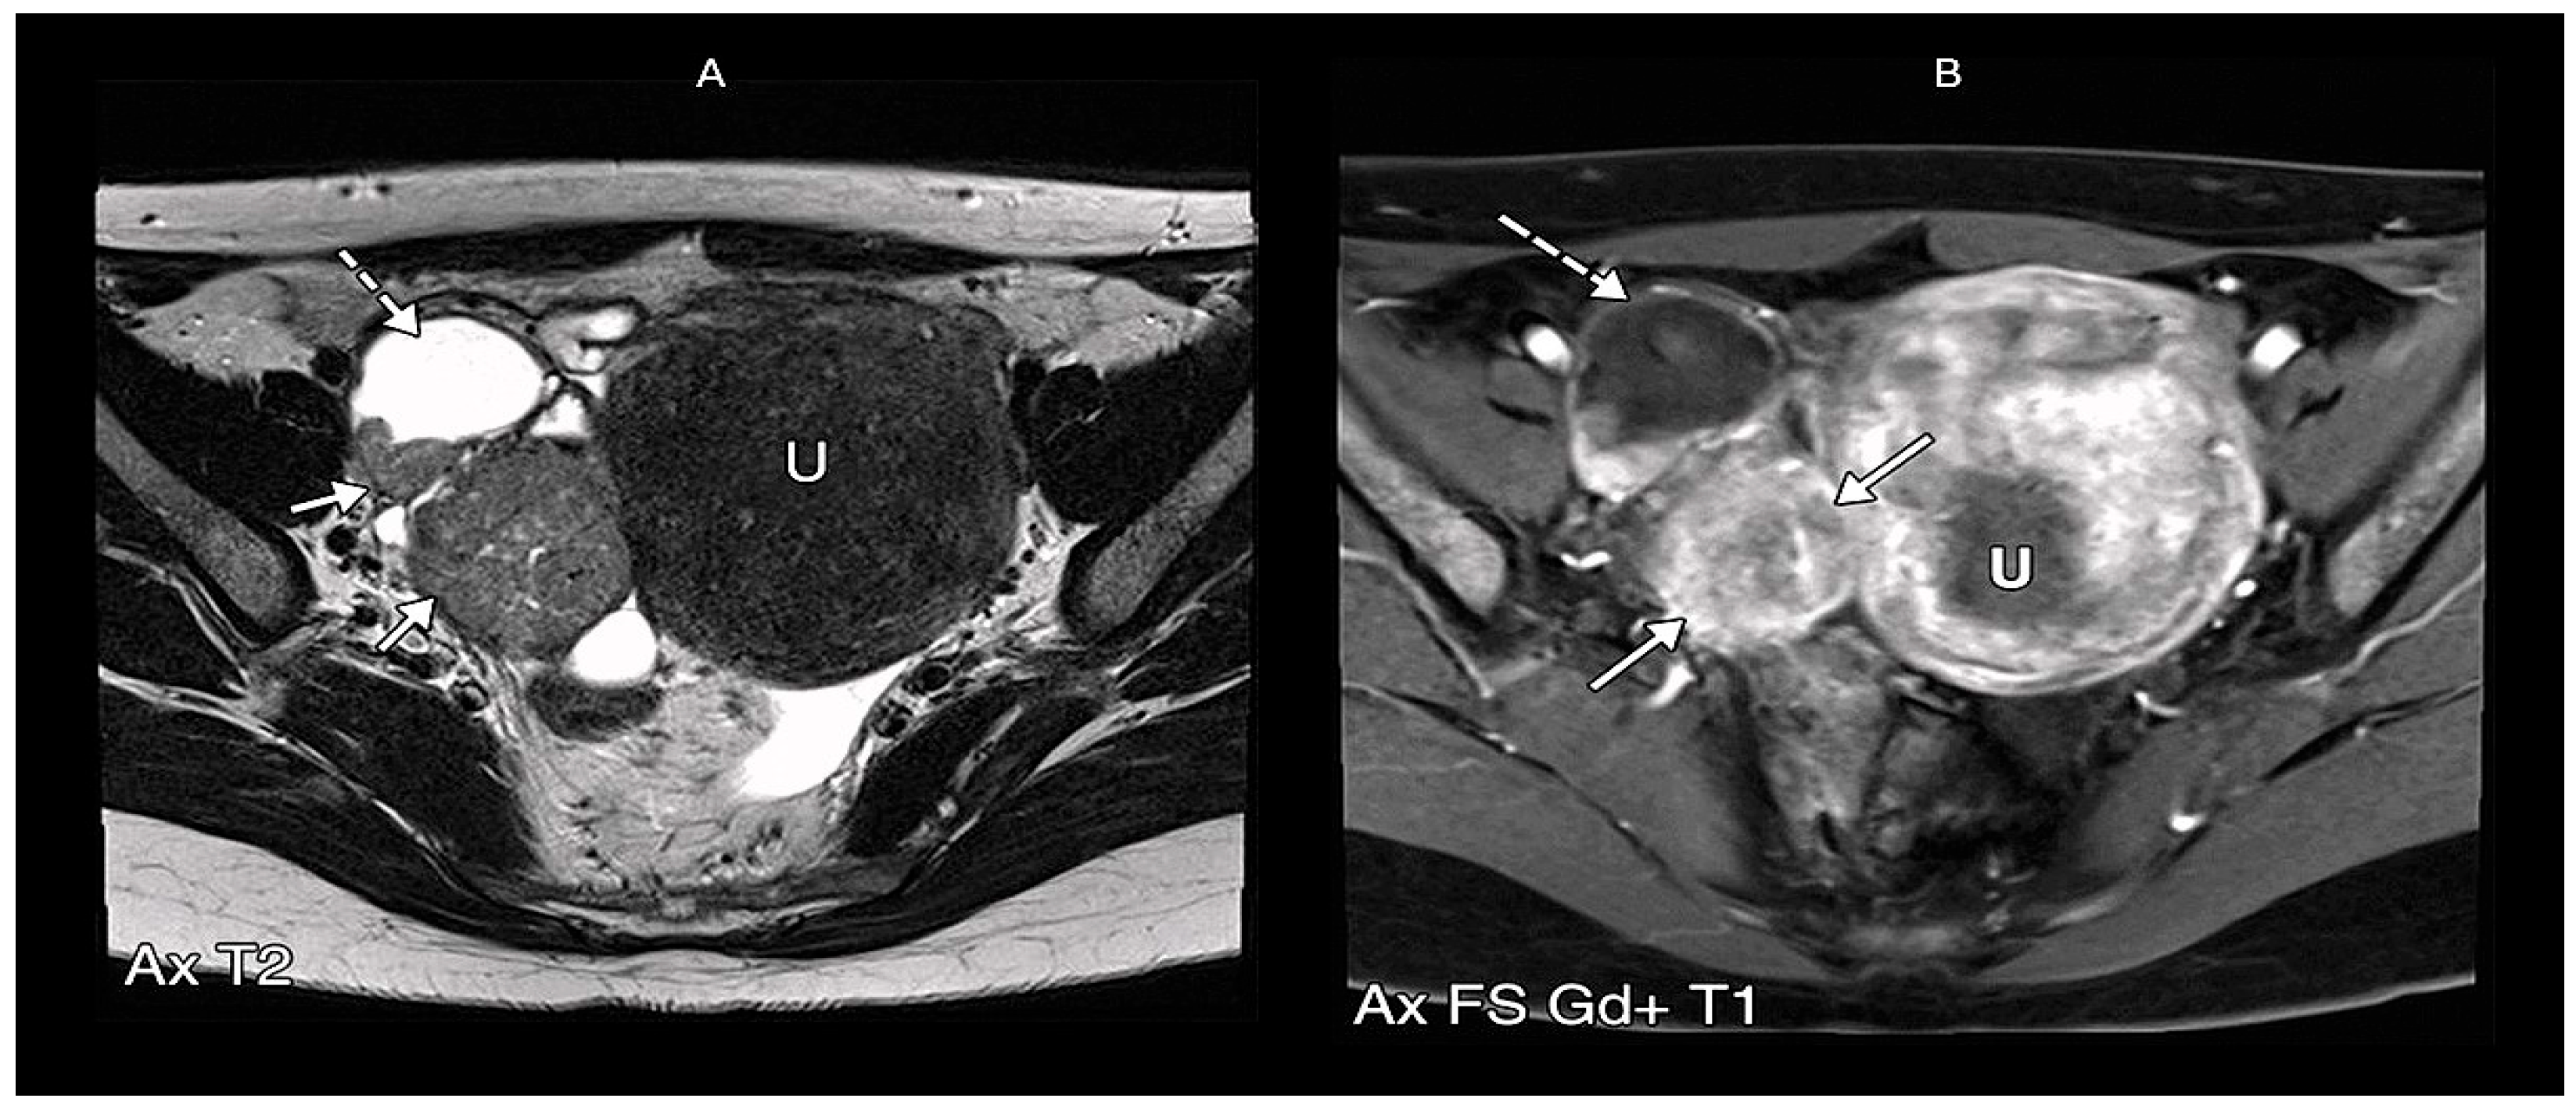

5.2. Magnetic Resonance Imaging

The O-RADS MRI Score and Its Implications for PFTC Diagnosis

- Ma, F.H.; Cai, S.Q.; Qiang, J.W.; Zhao, S.H.; Zhang, G.F.; Rao, Y.M. MRI for differentiating primary Fallopian tube carcinoma from epithelial ovarian cancer. J. Magn. Reson. Imaging JMRI 2015, 42, 42–47. [Google Scholar] [CrossRef]

| Morphology | Tubular/sausage-shaped mass |

| Enhancement Pattern | Continuous thick rim enhancement (>2.3 mm) |

| T2 Signal | Hyperintense tubular structure |